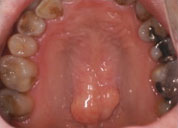

- PROTUBERANCE

- 骨隆起

- 上顎(口蓋隆起)

- 下顎